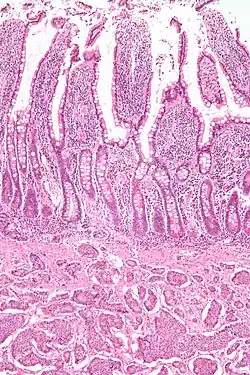

| Micrograph of a neuroendocrine tumor. H&E stain. | |